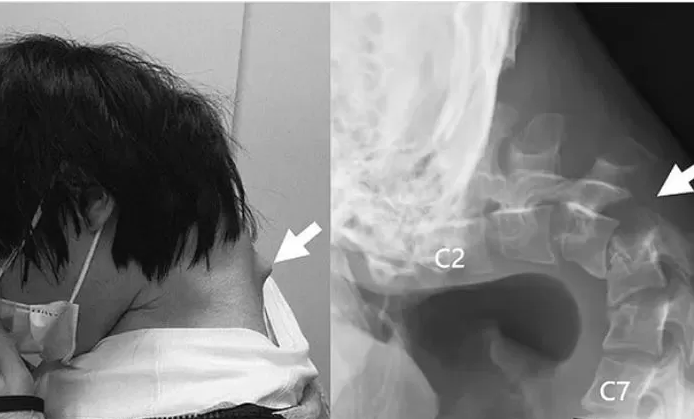

Jayada Phone Dekhne Par 25 Sal ke Admi ko Huya Yeh rog : “Droping Head Syndrome”

Droping Head Syndrome जापान के एक 25 साल की नौयवन को ज्यादा फ़ोन देखने पर हुआ यह बीमारी डॉक्टर ने डाइगोनोसिस के बाद बताया इस बोमरी को ” Droping Head Syndrome” कहते है । बहत टाइम तक फ़ोन देखने पर गर्दन पर इसतरह के बीमारी देखने को मिलती है । 25 साल जपनीस मन ने […]